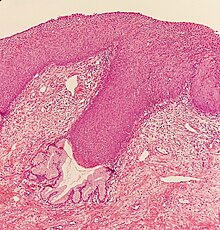

CIN is classified in grades:[17]

| Histology grade | Corresponding cytology | Description | Image |

|---|---|---|---|

| CIN 1 (Grade I) | Low-grade squamous intraepithelial lesion (LSIL) |

|

| CIN 2/3 | High-grade squamous intraepithelial lesion (HSIL) |